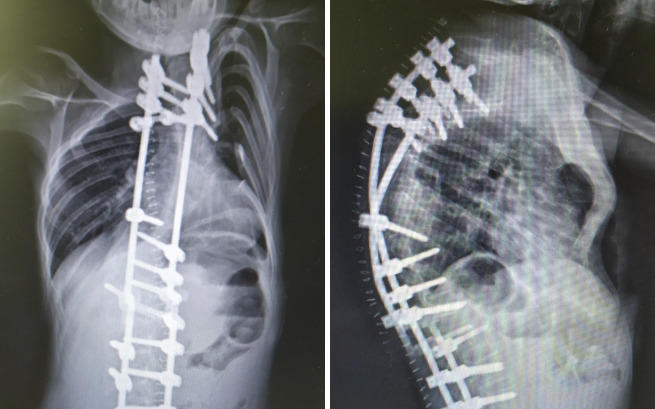

Michał od urodzenia cierpi na zespół wad wrodzonych. Los niestety nie był łaskawy i zesłał na niego wiele trudności, jedną z nich jest skolioza. Wszystko to sprawiło, że Michał od zawsze wymagał stałej opieki.